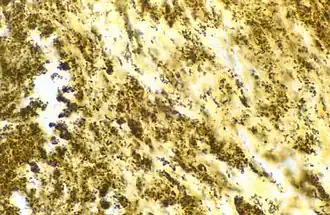

| Bacilo de Bartonella henselae (grânulos escuros) em válvula cardíaca de paciente com endocardite. | |